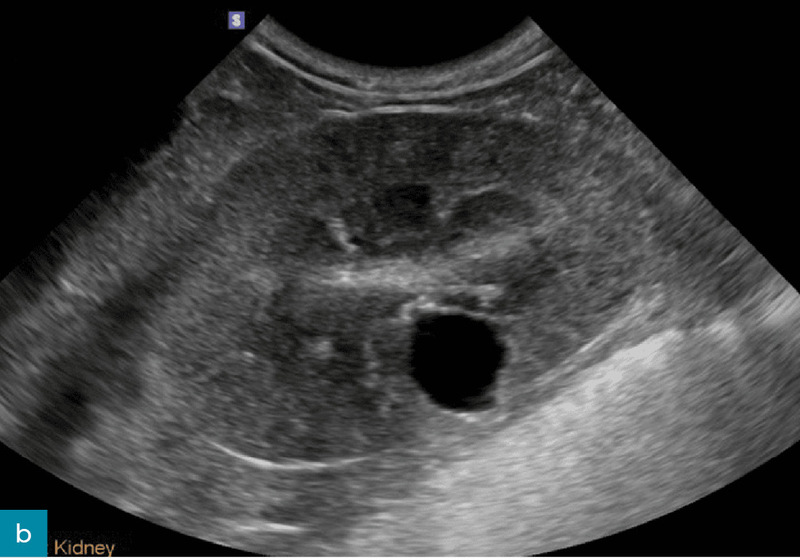

Poszerzenie miedniczki nerkowej (pielektazja)

Poza takimi czynnikami jak dożylna płynoterapia lub odmiedniczkowe zapalenie nerek zwiększone wydalanie moczu u pacjentów z przewlekłą chorobą nerek jest często związane z poszerzeniem miedniczki nerkowej.16 Pielektazja to nagromadzenie płynu i wtórne rozszerzenie miedniczki nerkowej wynikające z procesu niezwiązanego z niedrożnością (ryc. 8).8 Dla porównania wodonercze to rozszerzenie miedniczki nerkowej wtórne do niedrożności dróg moczowych. Pielektazja jest najczęściej symetryczna i obustronna, może jednak występować jednostronnie lub asymetrycznie w obu nerkach.3,16 U pacjentów z pielektazją i niewydolnością nerek wysokość miedniczki nerkowej zazwyczaj nie przekracza 3,4 mm u psów i 3 mm u kotów.16 Jeżeli poszerzenie miedniczki nerkowej jest większe, należy dokładnie ocenić drogi moczowe pod kątem nieprawidłowości, aby potwierdzić obecność innych procesów chorobowych, takich jak odmiedniczkowe zapalenie nerek lub wodonercze wtórne do niedrożności dróg moczowych.16

Ryc. 8. Obraz w projekcji poprzecznej prawej nerki psa, ukazujący łagodne poszerzenie miedniczki nerkowej (wysokość miedniczki nerkowej oznaczona wskaźnikami). Brak cech niedrożności.